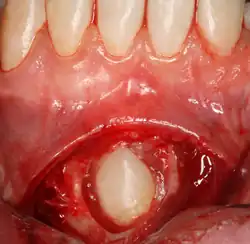

Die Oralchirurgie ist ein Teilgebiet der Zahnmedizin, das „die zahnärztliche Chirurgie einschließlich der Behandlung von Luxationen und Frakturen im Bereich der Zahn-, Mund- und Kieferheilkunde (Kieferbruchbehandlung) sowie die entsprechende Diagnostik“ (Musterweiterbildungsordnung (MWO) der Bundeszahnärztekammer[1], § 14 (2)) umfasst.

Die MWO[1] listet in Anhang 3 einen umfangreichen Operationskatalog auf, der während der Weiterbildung nachgewiesen werden muss. Hierzu gehören unter anderem:

- operative Weisheitszahnentfernung

- Entfernung verlagerter Zähne